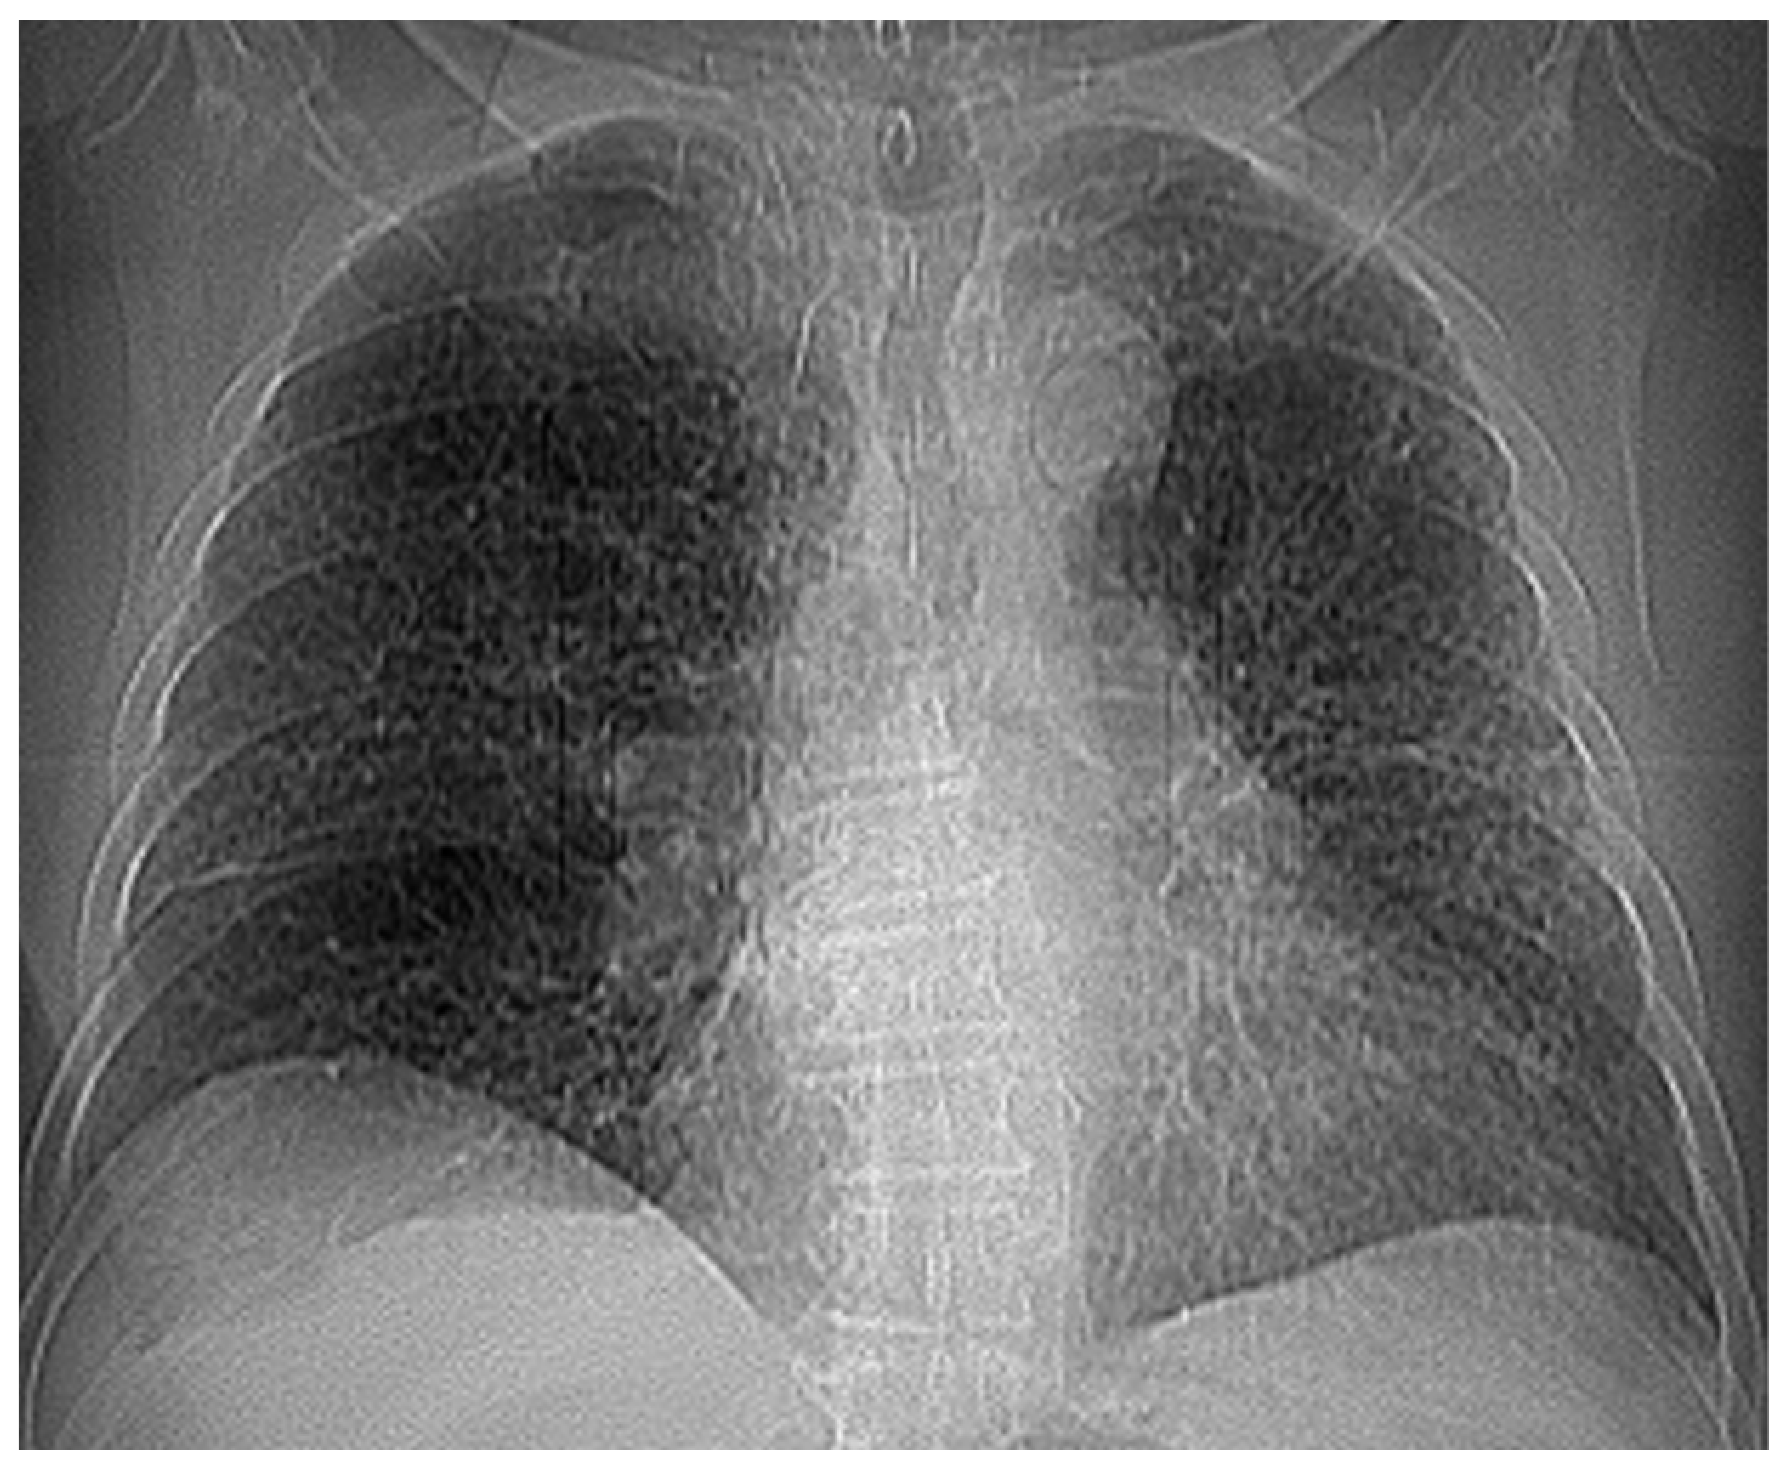

Several patients with a preliminary diagnosis of COVID-19 were tested using CT imaging with the contrast substance OMNIPAQUE 350. The pulmonary CT images obtained for each patient, along with their detailed fractal analysis, are presented in Figure 1, below.

Figure 1. (a) The CT scan image of a 69-year-old patient who underwent a chest CT examination due to suspicion of COVID-19 in the lungs. (b) A schematic representation of the pre-processing phases of the patient’s CT image (2D), which was resampled to an isomorphic resolution. The indices 5, 14, and 16 represent the numbers of the slices in order.